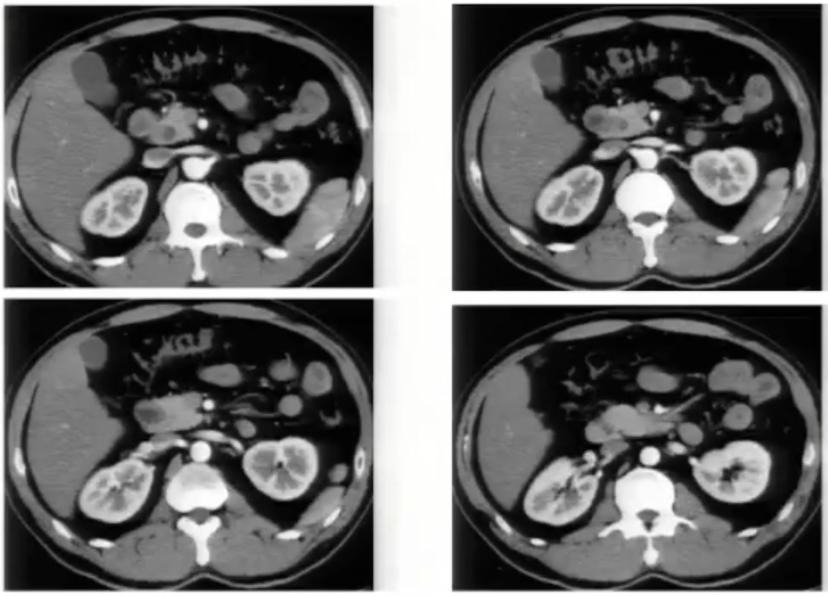

肾癌伴血管结构畸形

肾癌伴血管结构畸形患者的血管结构畸形往往容易被忽视。 在手术的过程中,如不注意就可能造成肝右叶血流的回流障碍,导致严重的临床后果。

图1:腹膜后方下腔静脉处于腹主动脉左侧;左肾静脉出左肾门后,汇入下腔静脉路径缩短

图2:冠状位重建显示下腔静脉肝段和肝下段缺如,向上直接延续为奇静脉